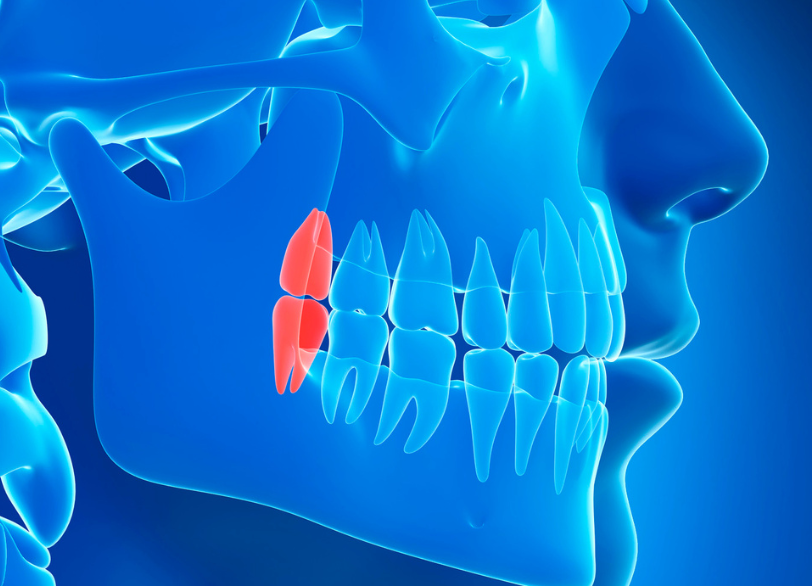

親知らずは専門的には「第三大臼歯」と呼ばれ、前歯から数えて8番目、一番奥に生えてくる永久歯です。多くの場合、10代後半から20代前半頃に生え始めますが現代人は食生活の変化などから顎が小さくなる傾向にあり、親知らずがきちんと生えるためのスペースが不足していることがほとんどです。

そのため横向きや斜めに傾いて生えたり、骨の中に完全に埋まったままだったりと正常な位置に生えてこられないケースが非常に多く見られます。

安全な抜歯を行う上で最も重要なのが、術前の精密な診査・診断です。特に下顎の骨の中には「下歯槽神経(かしそうしんけい)」という下唇の感覚などを司る太い神経が通っています。

親知らずの根の先がこの神経に近接している、あるいは接触しているケースも珍しくありません。

当院ではこのような複雑なケースや骨の中に深く埋まっている親知らずの抜歯を行う際には、必ず「歯科用CT」による撮影を行います。

従来の平面的なレントゲン写真では分からなかった親知らずの根の立体的な形や、神経・血管との正確な位置関係を三次元的に把握することができます。

このCTによる詳細な情報が手術中の神経損傷などの偶発的な事故を未然に防ぎ、安全で確実な抜歯計画を立てるための絶対的な基盤となるのです。